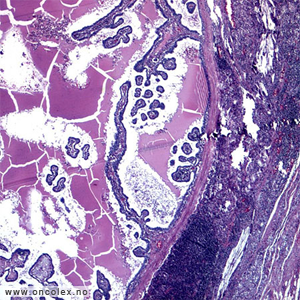

Bildeeksempler

Histologisk klassifikasjon (WHO)

• Papillær skjoldbruskkjertelkreft (cirka 70 %)

• Follikulær skjoldbruskkjertelkreft (cirka 15 %)

• Lite differensiert skjoldbruskkjertelkreft (under 5 %)

• Udifferensiert anaplastisk skjoldbruskkjertelkreft (under 5 %)

• Medullær skjoldbruskkjertelkreft (5-10 %)

• Andre

De fire første hovedgruppene utgår fra folliklenes overflateceller, mens medullær kreft utgår fra de såkalte C-cellene (kalsitoninproduserende) som er lokalisert i grupper mellom folliklene.